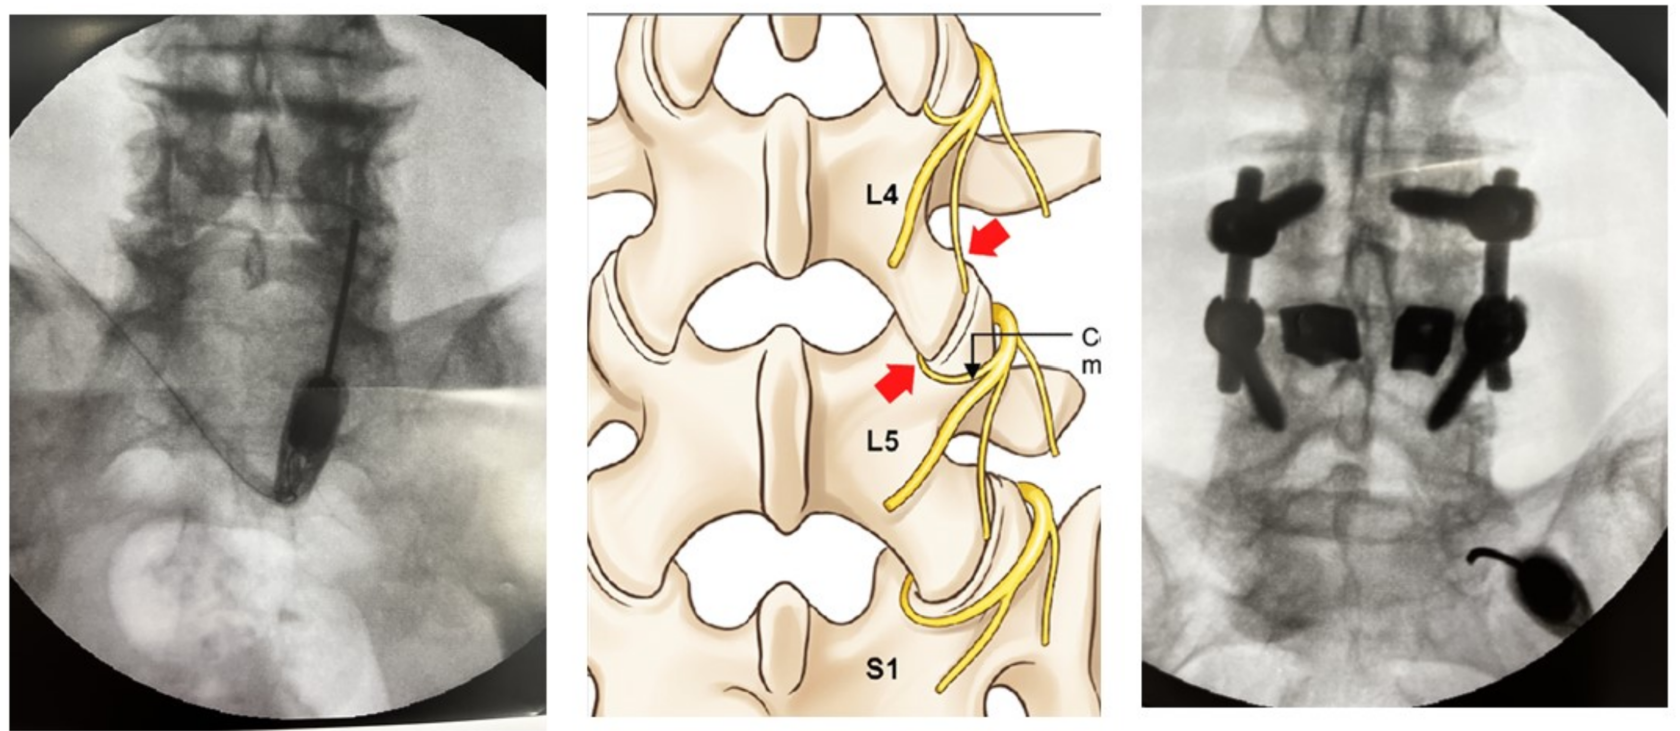

Лечение боли при фасеточном синдроме на поясничном отделе позвоночника

• N=50. Успех 62% через 1 год, лучше результаты у

неоперированных. C.B. Bärlocher, J.K. Krauss, R.W. Seiler. Kryorhizotomy: an alternative technique for lumbar medial branch rhizotomy in lumbar facet syndrome. J Neurosurg (Spine 1) 98:14–20, 2003.

• N=46. Успех 72% через 6 нед и 57% через 1 год. C Birkenmaier, A Veihelmann, H Trouillier et al. Percutaneous cryodenervation of lumbar facet joints: a prospective clinical trial. Int Orthop. 2007 Aug;31(4):525-30.

• N=76. Успех 56% через 1 год. M. Staender, U.Maerz, J.C. Tonn, U. Steude. Computerized tomography-guided kryorhizotomy in 76 patients with lumbar facet joint syndrome. J Neurosurg Spine 3:444 449, 2005.

Методика Bogduk, Dreyfuss

Альтернативная методика (Ambrock и др.)

Какая методика установки криозонда к фасеточным суставам лучше?

• Интенсивность боли после криоанальгезии была меньше, если предварительно проводили блокаду медиальных ветвей по сравнению с перикапсулярной блокадой через 6 недель и 3 месяца (ВАШ 2.2 v4.2, Р .05).

• C. Birkenmaier, A. Veihelmann, H. Trouillier et al. Medial Branch Blocks Versus Pericapsular Blocks in Selecting Patients for Percutaneous Cryodenervation of Lumbar Facet Joints. Regional Anesthesia and Pain Medicine, Vol 32, No 1 (January-February), 2007: pp 27-33